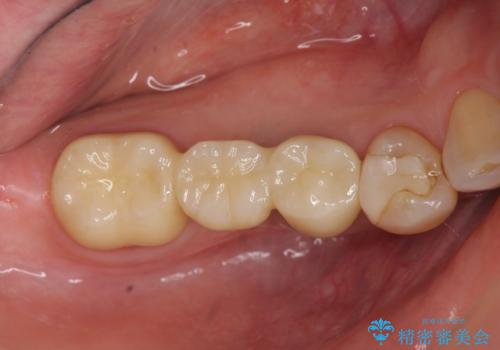

「ブリッジのところで噛むと痛い」 神経組織が原因の咬合痛

- 「以前治療して装着した右下のブリッジの部分で噛むと痛い、何もしなくても痛い」、と治療を希望され来院されました。

X線写真より歯の神経組織が壊死し、根尖周囲に病変を作り透過像を呈している状態でした。

咬合痛の原因となっている右下第2大臼歯の根幹治療を行ったのち、強度に優れるフルジルコニアクラウンによる咬合機能回復を計画します。